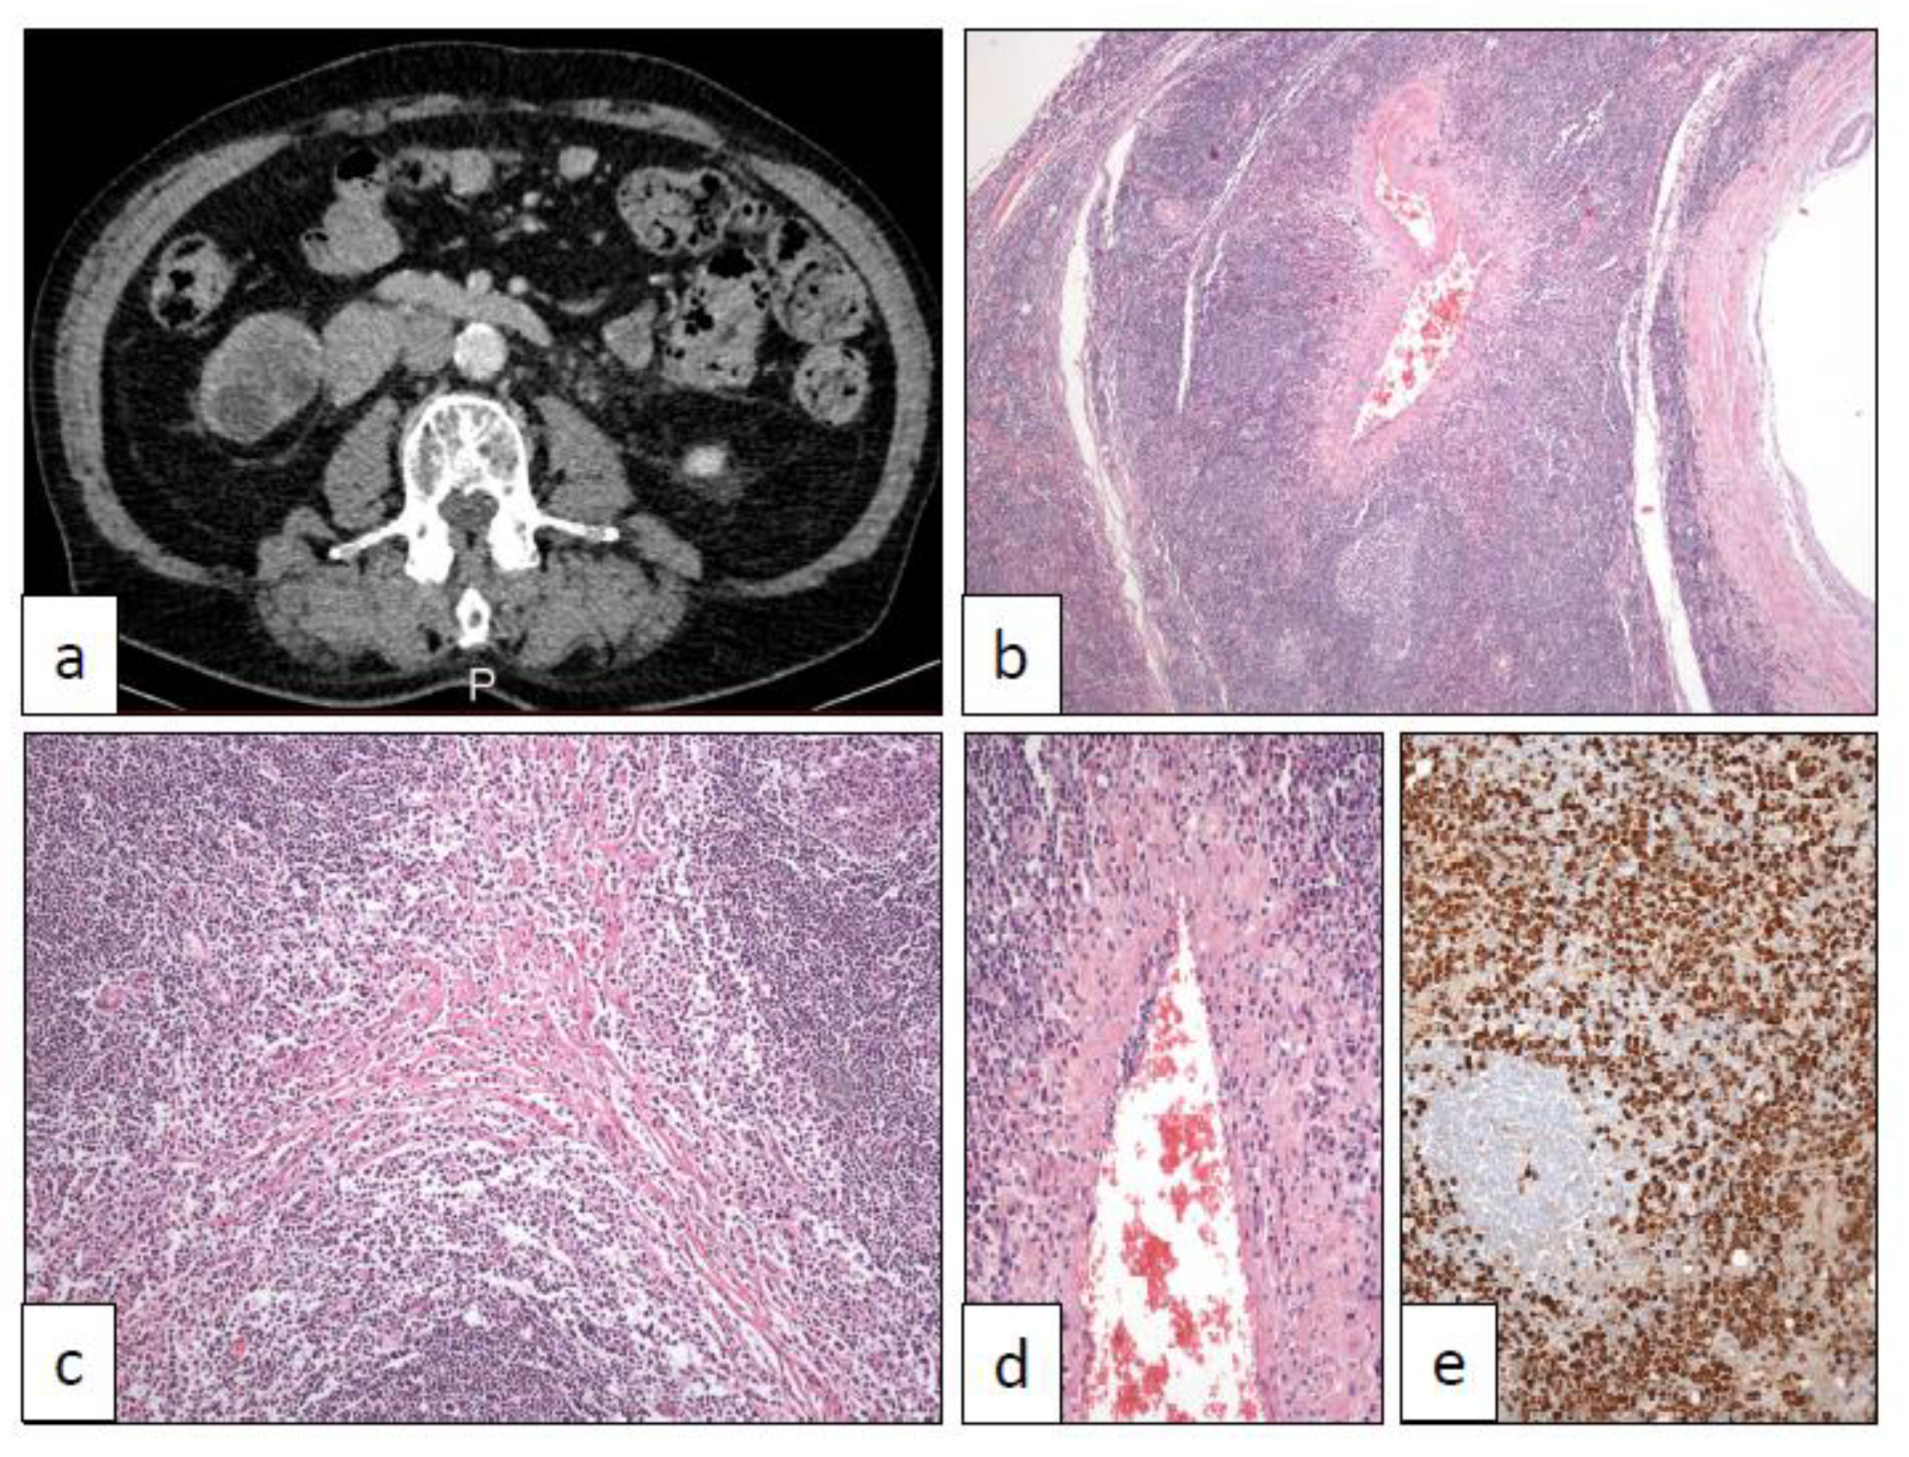

15. IgG4-Related Disease (IGG4)